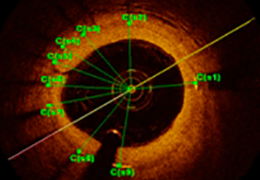

Performs 3D reconstruction and volume rendering.

Multi-planar slicing.

Oblique slicing.